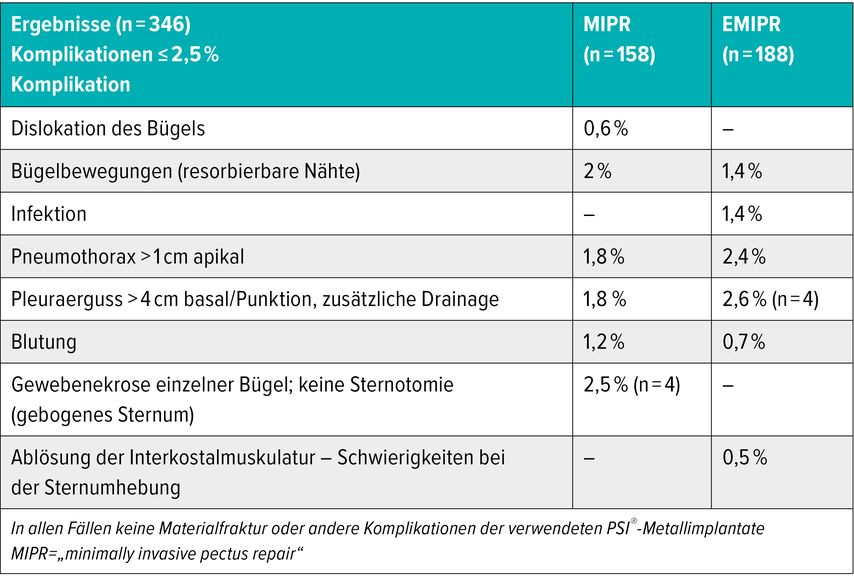

Die postoperative Komplikationsrate liegt unter ≤2,5% (Tab.1).

Tab. 1: Komplikationsraten nach einfacher MIPR und erweiterter Trichterbrustkorrektur (EMIPR) (A. Rokitansky)